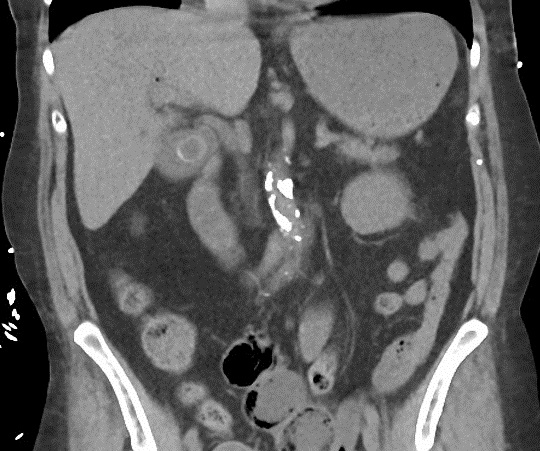

Dilatation systematise des voies biliaires

intrahepatique et de voie biliaire

commune avec des nodules calcifies (

hepatolithiasis ) . Aspect radiologique

a susgestion d'une cholangite sclerosant

primitive . Image TDM en coupe axiale

( non contrast ) |

|

Image de dialtation des voies

biliaires intrahepatique . Foie est elargir

et rude , veine porte dilate ,

splenomegalie , n' a pas de calcul biliaire

. Cholangite sclerosant primitive du foie en

coupe frontale ( TDM plus C+ ) |

Image radiologique de

cholangio TDM intraveineuse : Voie

biliare et vesicule biliaire retrouve tres nette , voie biliaire gauche est

dilate en segment multiple et

l'abcense de calcule de

voie biliaire . Cholangite sclerosant

primitive (CSP ) |